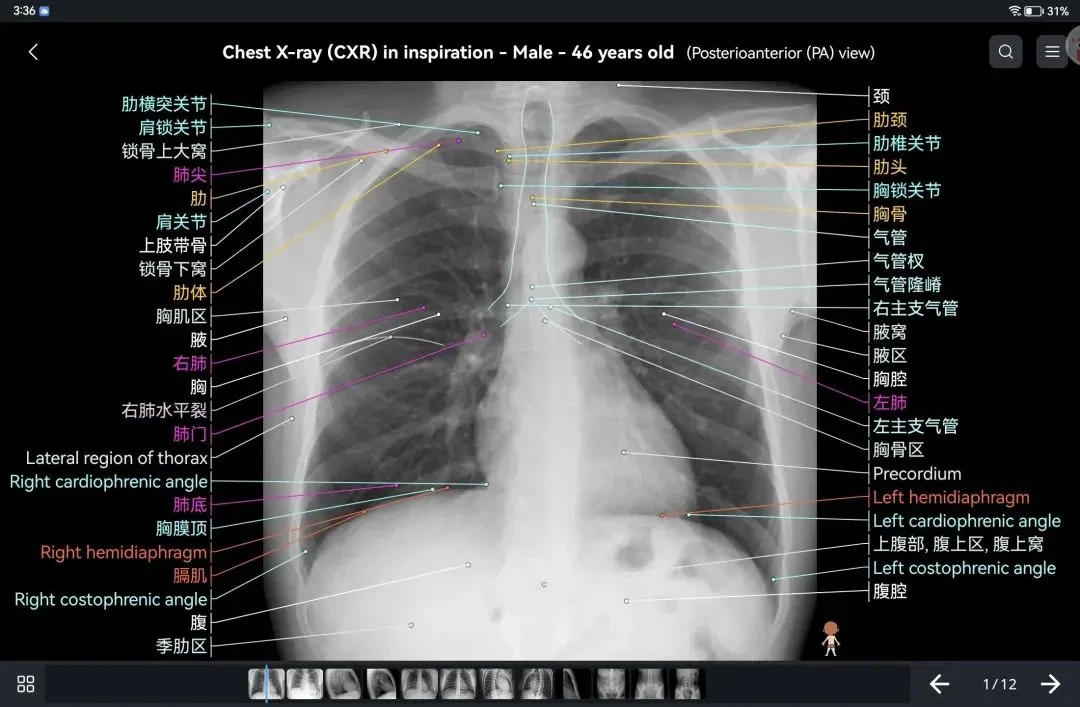

覆盖了X光、CT、MRI、断层大体解剖、核医学、介入造影、医学插图等多个模块,覆盖全身各个系统的影像解剖(正常解剖结构,无病例),其中的解剖结构高达87万个,结构标注超精细,超高清图像,历时两年研发设计完成✅。